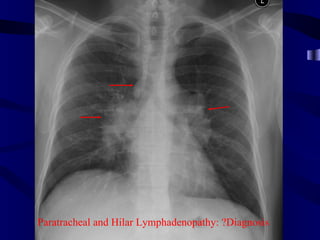

Paratracheal and Hilar Lymphadenopathy: ?Diagnosis

Bilateral Hilar Enlargement •Causes of bilateral hilar lymphadenopathy – Sarcoid – Tumors, e.g. lymphoma, bronchial carcinoma, metastatic tumors – Infection, e.g. tuberculosis, recurrent chest infections, AIDS – Berylliosis • Causes of pulmonary hypertension – Obstructive lung disease, e.g. asthma, COPD – Left heart disease, e.g. mitral stenosis, left ventricular failure – Left to right shunts, e.g. ASD, VSD – Recurrent pulmonary emboli – Primary pulmonary hypertension

Paratracheal and HilarLymphadenopathy: ?Diagnosis